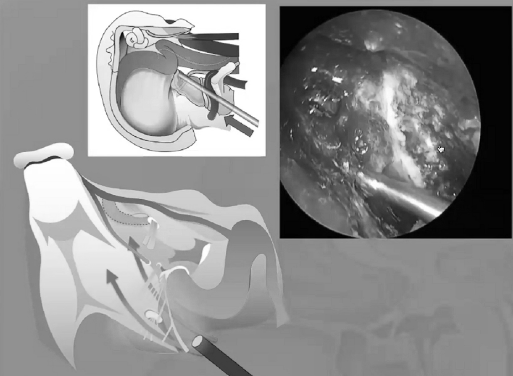

“筷子手法”经鼻内镜入路处理颅颈交界区肿瘤

从内镜我们怎样暴露颅颈交界区,需要把后方的咽部的黏膜和肌肉移开,如果我们要往侧方走的话,这比较具有挑战性,需要切掉一半的下方的结节,我们需要切除更多的黏膜,更多的肌肉,还需要磨掉翼板的内侧,要注意颈内动脉的二个膝部,还得切除一部分的咽鼓管,还得磨除一部分的枕髁,才能到达侧方,这样是很耗精力的。

▼下图所示案例肿瘤看着很大,然后用30度、45度甚至70度的内镜,我们有很多带角度的器械,利用这些器械就可以切除肿瘤。可以先切开黏膜,然后把蝶窦内的黏膜推开,然后进入肿瘤。目前我们正在努力的开发这方面的器械,没有这些器械我们是做不了手术的。

▼下面就是我所说的有角度的器械,然后我们用脂肪来修补,我们在内镜下做缝合,在内镜下做缝合很复杂难度很大,所以很花时间,但是它是值得的。